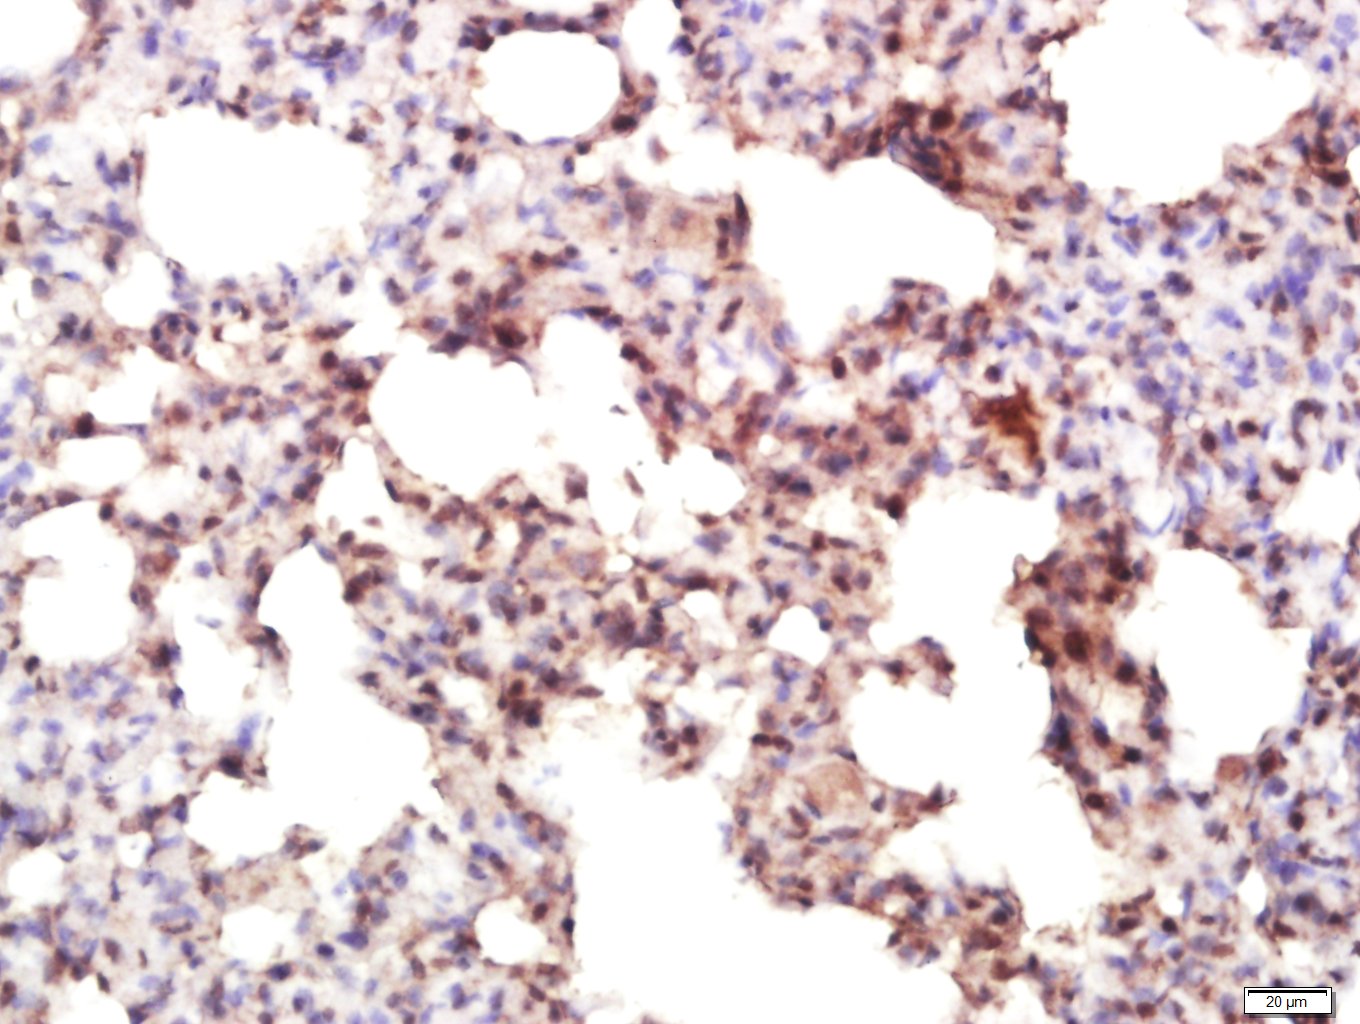

| 英文名称 | IRF7 Rabbit pAb |

| 中文名称 | 干扰素调节因子7抗体 |

| 产品应用 | IHC-P=1:100-500, IHC-F=1:100-500, IF=1:100-500, Flow-Cyt=1ug/test Not yet tested in other applications. |

| 交叉反应 | Mouse, Rat (Human, Dog, Pig, Cow, Rabbit) |

| {IHC-P} | {1:100-500} |

| {IHC-F} | {1:100-500} |

| {IF} | {1:100-500} |

| {Flow-Cyt} | {1ug/test} |